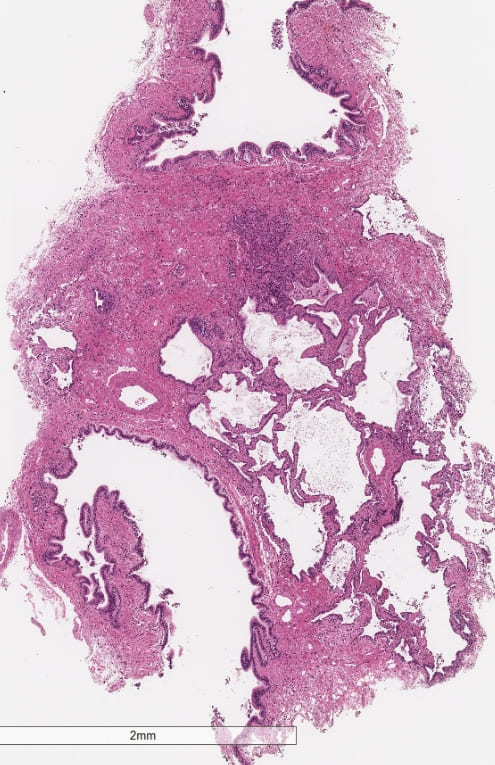

【クライオ肺生検組織】

右B8a:拡張気管支と、周囲の肺胞に細気管支上皮の被覆及び胞隔の線維性肥厚。

右B8b:拡張気管支と、周囲の肺胞の虚脱を伴う線維化。拡張した気腔にせり出す幼弱な線維芽細胞巣。

#fNSIP+UIPの混在